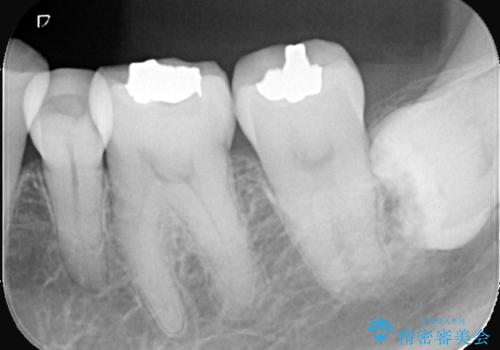

- 主訴:口を開けると所々入っている銀の詰め物が目立つので白い物にやり替えたい。

下顎大臼歯部に入っている保険適用のメタルインレーを、適合性と審美性の良いセラミックインレーでのやり替えとなりました。

メタルインレーを除去した際、古い裏層材やカリエスは除去し新たにCR裏層しています。